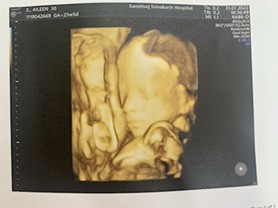

รูปนี้ตอนน้อง 21 week. ยังไม่ค่อยมีแก้ม ตอนนี้น้อง 30+3 week. แม่อยากซาวด์อีก ตอน 32 week. ดูหน้าก่อนคลอดค่ะ